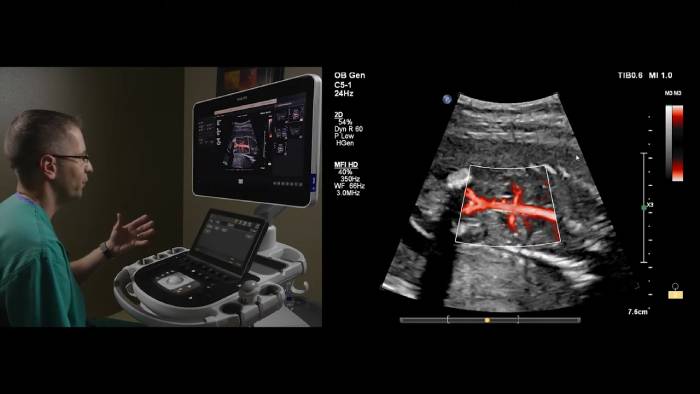

En este vídeo el Dr. Michael Ruma, de Perinatal Associates, Nuevo México (EE. UU.), explora el uso de Philips MFI HD en aplicaciones fetales con los transductores eL18-4 y C5-1.